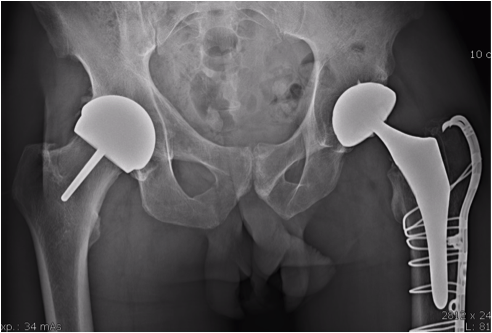

Le resurfaçage de hanche est un remplacement articulaire qui diffère d'une prothèse totale de hanche classique. Dans le resurfaçage, le col fémoral est conservé et la tête fémorale n'est pas retirée mais retaillée pour recevoir l'implant. Au niveau du bassin, la cavité acétabulaire est moins creusée que pour une prothèse conventionnelle. Cela aboutit à une économie maximale du stock osseux.

Cupule de resurfaçage de hanche

Cupule de resurfaçage

Prothèse de resurfaçage de hanche

Prothèse de resurfaçage en place

Dans une prothèse totale, la tête fémorale est retirée et remplacée par une tige métallique insérée dans le fémur. Dans le resurfaçage, la tête est conservée et simplement retaillée pour recevoir un capuchon métallique. Le col fémoral est préservé. L'avantage principal : une économie maximale d'os, facilitant un éventuel changement ultérieur, et la possibilité de pratiquer tous les sports sans restriction.